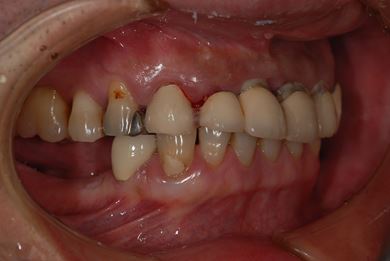

インプラントの症例写真 IMPLANT

骨再生スピードインプラント治療+セラミック治療

| 性別/年齢 | 男性 / 53歳 | ||||||||||||||||||||||||||||||||

| 主訴 | インプラント治療の相談。 | ||||||||||||||||||||||||||||||||

| 治療方針 | 上前歯部は、抜歯と同時にインプラントを埋入し、治療期間を短縮する。左上奥は、ソケットリフトにて上顎洞を拳上し、インプラント治療を可能にする。 | ||||||||||||||||||||||||||||||||

| 治療内容 | インプラント4本(ソケットリフト・抜歯即日)、テンポラリーインプラント2本、メタルボンドクラウン9本 | ||||||||||||||||||||||||||||||||

| 総治療費 | 2,025,975円 | ||||||||||||||||||||||||||||||||

| 治療期間 | 1年9ヶ月 |